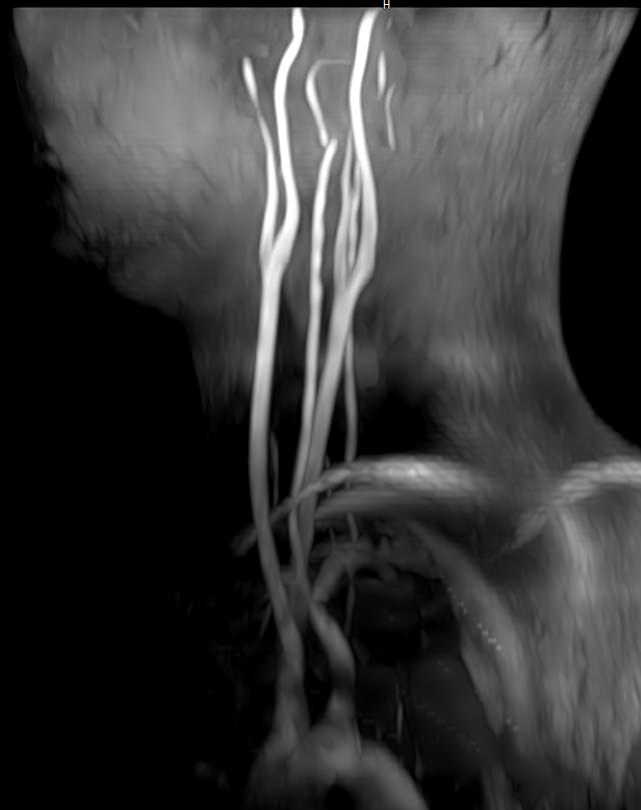

В клинике «Доступная медицина» проводится комплексное исследование: МР-ангиография шеи и головного мозга на новейшем высокопольном томографе экспертного уровня TOSHIBA VANTAGE TITAN 1,5 Тесла, который создает изображения сосудистой системы превосходного качества, что позволяет проводить точную диагностику и назначать пациенту своевременное лечение. МР-ангиография проводится в стандартном режиме без использования контраста.

- Суть исследования МРТ сосудов шеи и головного мозга

Суть исследования МРТ сосудов шеи и головного мозга

Для обнаружения заболеваний шеи, зачастую доктора назначают особые технологии проверки, например Доплер или рентген-анализ. Но бывают ситуации, связанные с вероятностью наличия в теле пациента аномальных процессов, происходящих в мягких тканях, тогда врачи выписывают направление на прохождение МРТ сосудов шеи. Подобное обследование показывает даже самые мелкие и незначительные изменения.